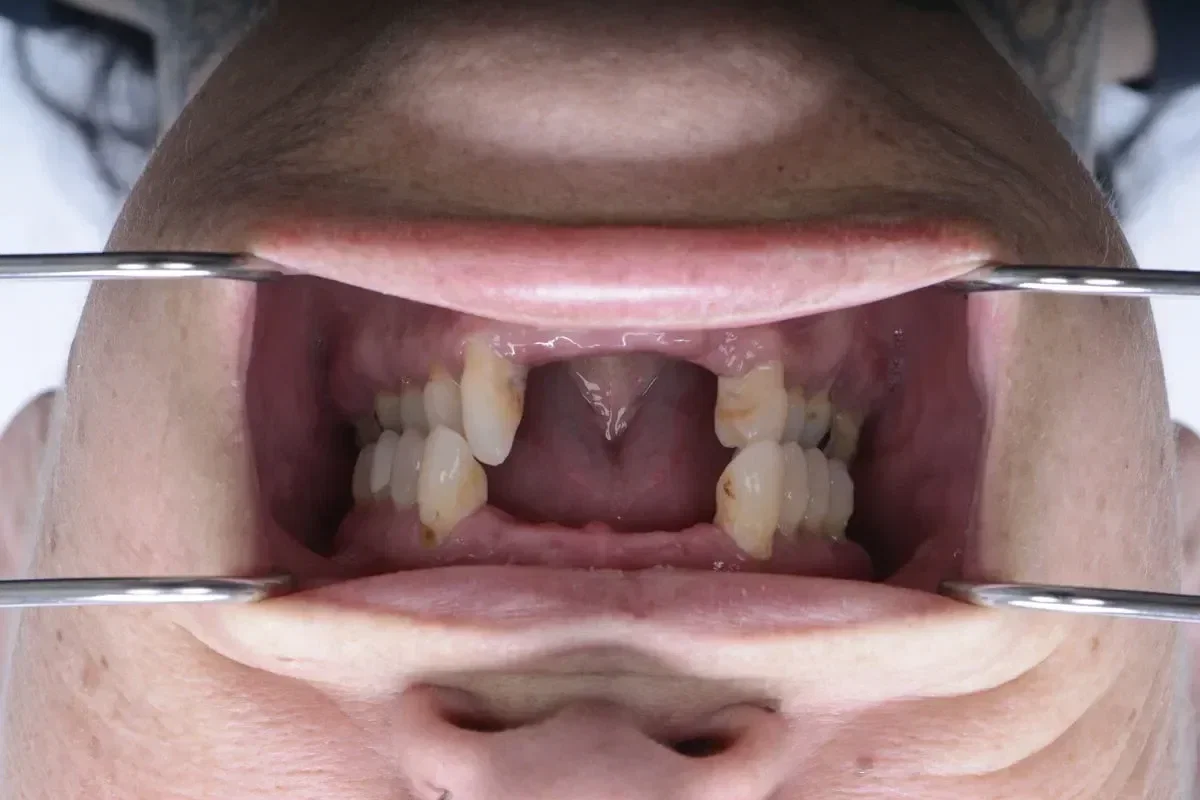

Real Smile Transformations

See the life-changing results from real patients who chose Fusion Dental Implants.